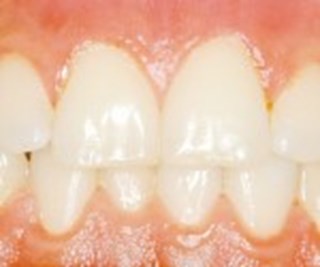

Tandkött

Ett sjukt tandkött är svullet och har större volym, jämfört med ett friskt som är i biologisk balans. När tandköttet läker efter en allvarlig parodontit kan det dra sig tillbaka något. Detta innebär sällan några problem funktionellt, men det kan medföra blottade tandhalsar och större mellanrum mellan tänder och tandkött.

En lätt inflammation i tandköttet läker vanligtvis ut på en dryg vecka. Förutsättningen är att eventuell tandsten tagits bort och att munnen hålls ren, enligt de instruktioner tandläkaren eller tandhygienisten gett.